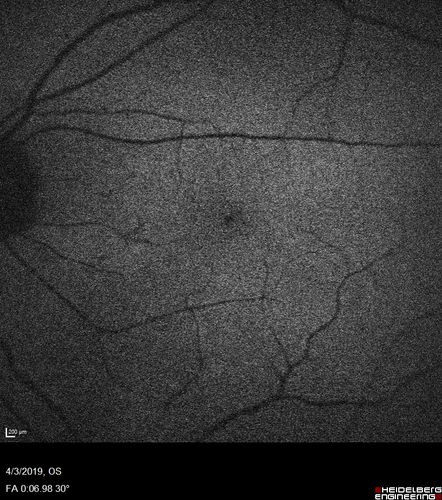

Stellate Non-heredtiary Idiopathic Foveomacular Retinoschisis (SNIFR)

77 year old man who is healthy and 6'6" tall with 20/40 vision and no complaints. OCT shows diffuse retinoschisis.